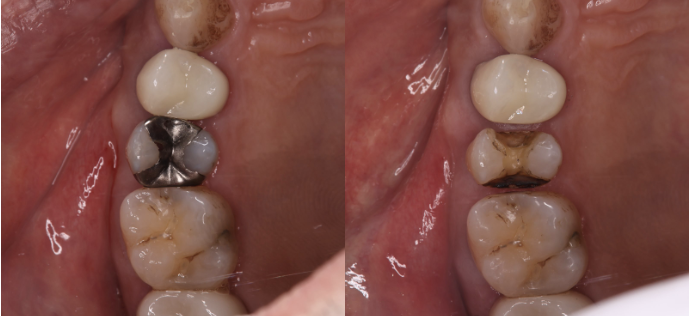

2次虫歯とは、一度虫歯治療した歯が再度虫歯になることを言います。虫歯治療を行う際に使用する詰め物は、金属プラスチックセラミックの3種類の素材が一般的に使用されます。その中でも、特に金属は虫歯の再発リスクが高いと言われています。

ことから歯と銀歯の隙間に虫歯菌が侵入し、銀歯の中で虫歯の再発が起こりやすいのです。実際に、銀歯の装着から5~7年後には虫歯の再発リスクが高いと言われています。

⒊銀歯を使用しないメタルフリー治療

歯科では、昔から銀歯を多く使用してきました。しかし、近年ではセラミックやプラスチックといった銀歯以外の素材を使用することが増えてきました。メタルフリー治療では、虫歯の再発リスクの低下、銀歯も用いない審美性の向上、金属アレルギーの心配もありません。